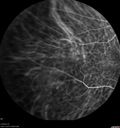

88 year old female with melanosis oculi and 2.5 mm elevated choroidal melanoma. She also has AMD with geographic atrophy. The right eye is the better eye. The left eye had a macular hemorrhage from wet AMD and breakthrough vitreous hemorrhage.